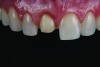

Fig 5. One-week follow-up of feldspathic porcelain veneer on tooth No. 8.

Figure 2